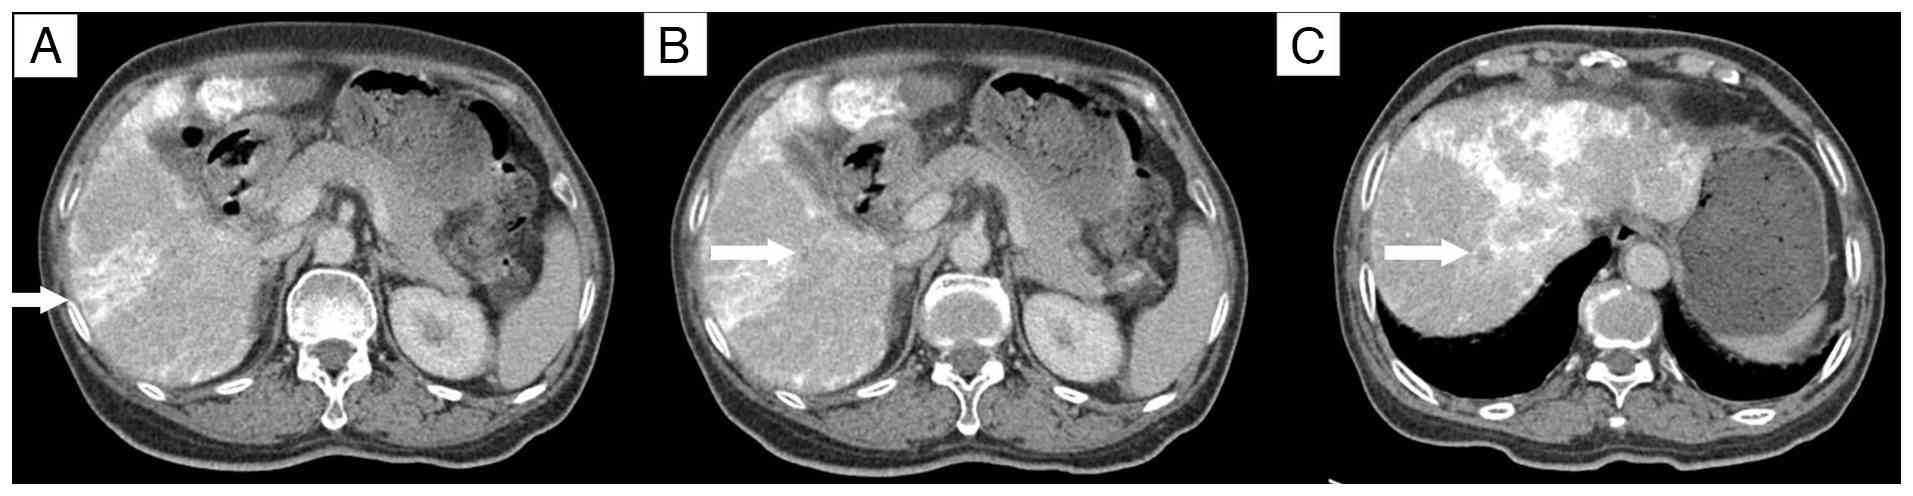

A total of 5 days after the initial chemotherapy treatment, the patient was admitted to the in the Department of Hepatobiliary Surgery and underwent RFA with a concurrent biopsy of the left hepatic lobe lesion. The postoperative pathology, performed as aforementioned, confirmed liver metastasis of colorectal cancer. The cells were arranged in irregular glandular structures with infiltrative growth, and the nuclei were enlarged, with prominent nucleoli (Fig. 3A). The patient developed abdominal pain and a fever following the operation. A CT scan 1 week after RFA revealed signs of infection (Fig. 3B and C), which recovered after antibiotic treatment. In October 2013, the chemotherapy regimen was switched to XELOX (1,500 mg capecitabine orally twice daily on days 1–14; 180 mg oxaliplatin by intravenous infusion on day 1), followed by TACE 8 days later, targeting the metastatic lesions in the right hepatic lobe. A contrast-enhanced CT scan conducted 10 days post-TACE showed no significant reduction in the size of the three lesions in the right hepatic lobe compared with the size in the images taken before the procedure, with persistent mild enhancement (Fig. 4).

Enhanced computed tomography scans

following transarterial chemoembolization. (A) The lesion beneath

the liver capsule in the right lobe shows no significant reduction

in size compared with before, with mild enhancement (arrow). (B)

The lesion adjacent to the portal vein in the right lobe still

shows mild enhancement (arrow). (C) The lesion at the apex of the

right lobe of the liver shows no significant reduction in size

compared with before, with mild enhancement (arrow).

Figure 4.

Enhanced computed tomography scans following transarterial chemoembolization. (A) The lesion beneath the liver capsule in the right lobe shows no significant reduction in size compared with before, with mild enhancement (arrow). (B) The lesion adjacent to the portal vein in the right lobe still shows mild enhancement (arrow). (C) The lesion at the apex of the right lobe of the liver shows no significant reduction in size compared with before, with mild enhancement (arrow).